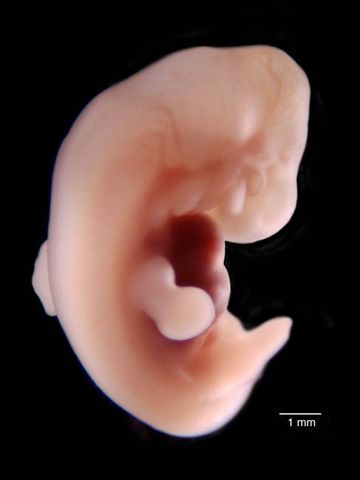

• 3 a.  Semana

3 a. Semana

Comienza a formarse la futura placenta, aparecen esbozos de vasos sanguíneos y de células sexuales, así como una tercera hoja del disco embrionario. Cada una de las tres hojas va a dar origen a tejidos especializados, que a su vez serán el origen de todas las demás células y, por lo tanto, de todos los órganos.

• 4 a Semana

4 a Semana

Período de transición entre la formación del embrión (embriogénesis) y la de los órganos (organogénesis) del futuro bebé. Los primeros latidos cardíacos se manifiestan hacia el 23.º día. El embrión adquiere su forma definitiva:El embrión flota en medio de la cavidad amniótica, unido a la parte externa del huevo por el cordón umbilical, que se está formando. Al final de este primer mes, el embrión mide 5 mm.